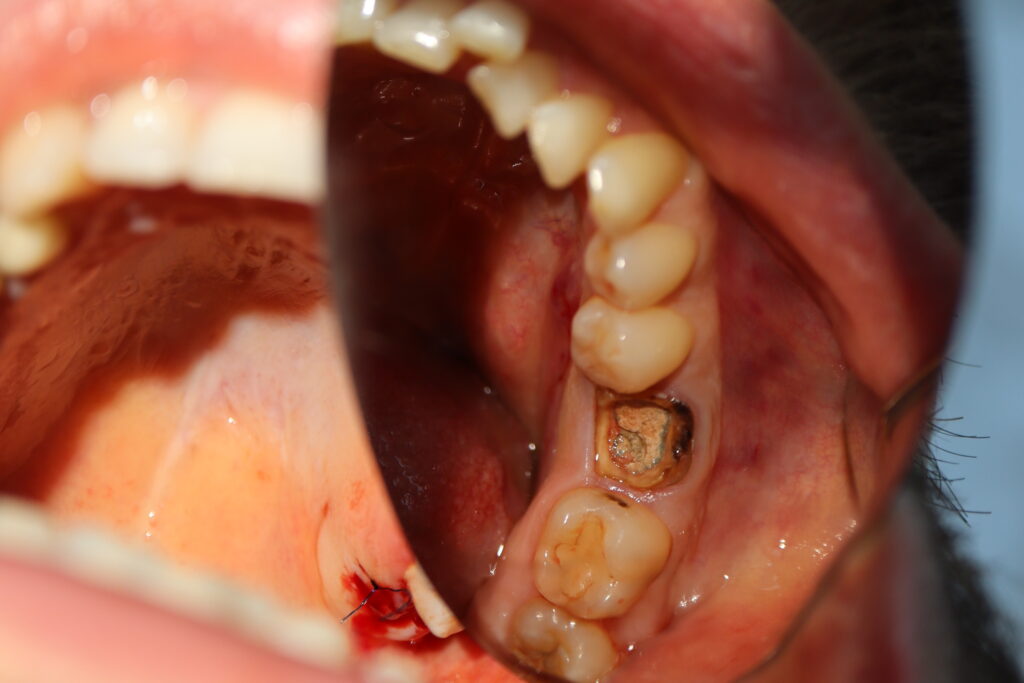

Процесс работы

Что было сделано:

За одно посещение был удален зуб 3.6 и установлен имплантат Megagen AnyOne, установлен формирователь десневой манжетки.

процедура имплантации

Это фото может содержать тяжелый для восприятия контент